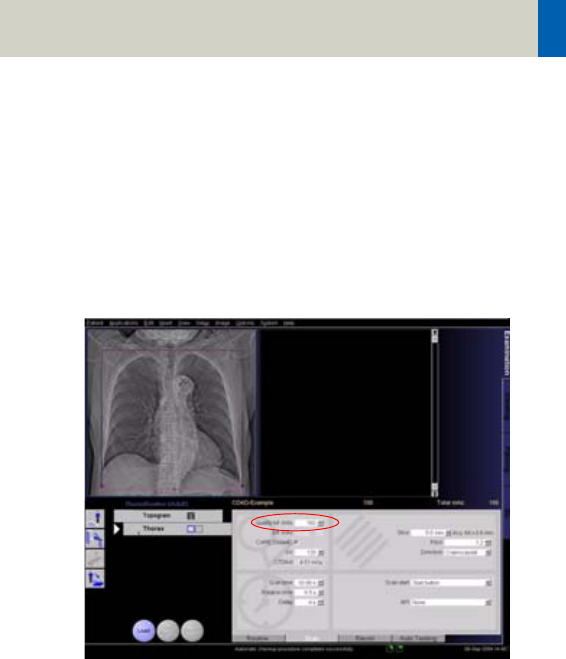

After the topogram has been scanned, the (eff.) mAs

value in the Routine tab card displays the mean (eff.)

mAs estimated by CARE Dose 4D based on the topo-

gram*. After the scan has been performed this value is

updated to the mean (eff.) mAs that was applied. The

values may differ slightly due to the online modulation

according to the patient’s angular attenuation profile.